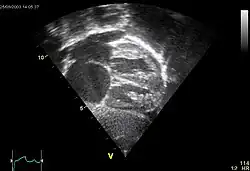

Echocardiography

In transthoracic echocardiography, an atrial septal defect may be seen on color flow imaging as a jet of blood from the left atrium to the right atrium.

If agitated saline is injected into a peripheral vein during echocardiography, small air bubbles can be seen on echocardiographic imaging. Bubbles traveling across an ASD may be seen either at rest or during a cough. (Bubbles only flow from right atrium to left atrium if the right atrial pressure is greater than left atrial). Because better visualization of the atria is achieved with transesophageal echocardiography, this test may be performed in individuals with a suspected ASD which is not visualized on transthoracic imaging. Newer techniques to visualize these defects involve intracardiac imaging with special catheters typically placed in the venous system and advanced to the level of the heart. This type of imaging is becoming more common and involves only mild sedation for the patient typically.

If the individual has adequate echocardiographic windows, use of the echocardiogram to measure the cardiac output of the left ventricle and the right ventricle independently is possible. In this way, the shunt fraction can be estimated using echocardiography.

-

ASD with pulmonary embolism resulting in a right-to-left shunting of blood[21]